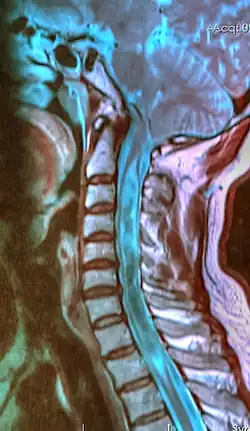

| A sagittal FLAIR MRI scan, from a patient with an Arnold–Chiari malformation, demonstrating tonsillar herniation of 7 mm. | |

Diagnosis is made through a combination of patient history, neurological examination, and medical imaging.[27][28] Magnetic resonance imaging (MRI) is considered the preferred imaging modality for Chiari malformation.[29] The MRI visualizes neural tissue such as the cerebellar tonsils and spinal cord as well as bone and other soft tissues. CT and CT myelography are other options and were used prior to the advent of MRI, unfortunately the resolution of CT based modalities do not characterize syringomyelia and other neural abnormalities as well.[30]

By convention, the cerebellar tonsil position is measured relative to the basion-opisthion line, using sagittal T1 MRI images or sagittal CT images.[31] The selected cutoff distance for abnormal tonsil position is somewhat arbitrary, as not every person will be symptomatic at a certain amount of tonsil displacement, and the probability of symptoms and syrinx increases with greater displacement; however, greater than 5 mm is the most frequently cited cutoff number, though some consider 3–5 mm to be "borderline"; pathological signs and syrinx may occur beyond that distance.[31][32][33] One study showed little difference in cerebellar tonsil position between standard recumbent MRI and upright MRI for patients without a history of whiplash injury.[25] Neuroradiological investigation is used to rule out any intracranial condition that could be responsible for tonsillar herniation first. Neuroradiological diagnostics evaluate the severity of crowding of the neural structures within the posterior cranial fossa and their pressure against the foramen magnum. Chiari 1.5 is a term used when both brainstem and tonsillar herniation through the foramen magnum are present.[34]